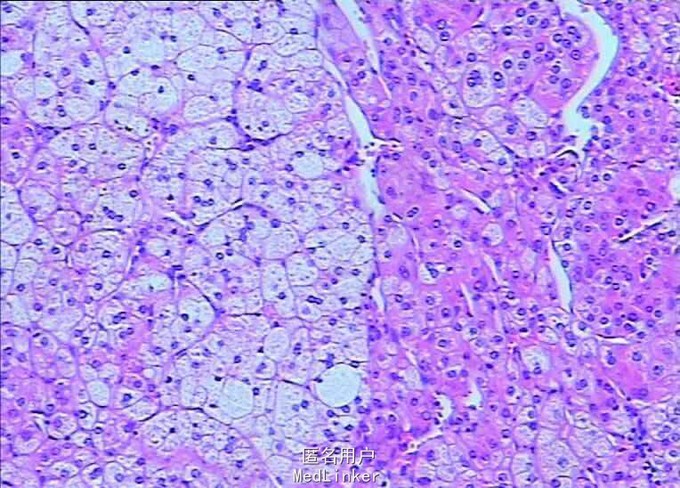

Bp:168/112mmHg,其余无特殊。 肾上腺CT:左侧肾上腺结节,考虑腺瘤可能性大。双肾、脾脏多发囊肿。双肾动脉CTA检查未见明确病变。左侧肾上腺见一大小约25mm×22mm的结节影,CT值约40HU,增强扫描可见强化。右侧肾上腺大小、形态及密度未见明确异常。 术后病理示肾上腺皮质腺瘤。

诊断:左侧肾上腺皮质腺瘤 在全麻下行“肾上腺切除术,经腹腹腔镜,术程顺利,术后恢复好。